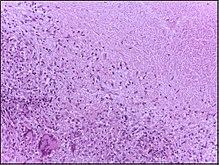

Microscopically, in a Wright's stained peripheral blood smear, a normal lymphocyte has a large, dark-staining nucleus with little to no eosinophilic cytoplasm. In normal situations, the coarse, dense nucleus of a lymphocyte is approximately the size of a red blood cell (about 7 μm in diameter).[11] Some lymphocytes show a clear perinuclear zone (or halo) around the nucleus or could exhibit a small clear zone to one side of the nucleus. Polyribosomes are a prominent feature in the lymphocytes and can be viewed with an electron microscope. The ribosomes are involved in protein synthesis, allowing the generation of large quantities of cytokines and immunoglobulins by these cells.